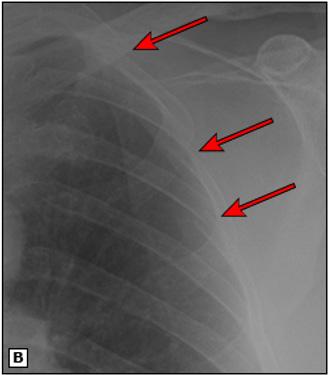

Figura 8.

(A) Una radiografía de tórax muestra una clavícula derecha rota con un gran neumotórax derecho y neumomediastino en una mujer de 24 años atropellada por un automóvil. (B) Una radiografía obtenida después de la colocación de un tubo torácico muestra un neumotórax persistente. Se observó una gran fuga de aire del tubo. La broncoscopia reveló una rotura completa del bronquio principal derecho